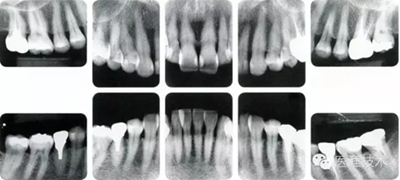

55歲牙周炎男性的臨床照片

55歲男性抽煙患者(1天20支、抽煙35年)。菌斑控制得不好。通過牙周探診,全頜有4~9mm的牙周袋,有1~3度的根分叉部病變。通過X光片觀察,上頜前牙中度牙槽骨吸收,其他地方有中度牙槽骨吸收。受吸煙影響,牙齦纖維性肥厚,呈紅黑色。牙齦幾乎沒有浮腫和發(fā)紅,所以這個病例是從外觀上無法預測病癥嚴重程度的病例。